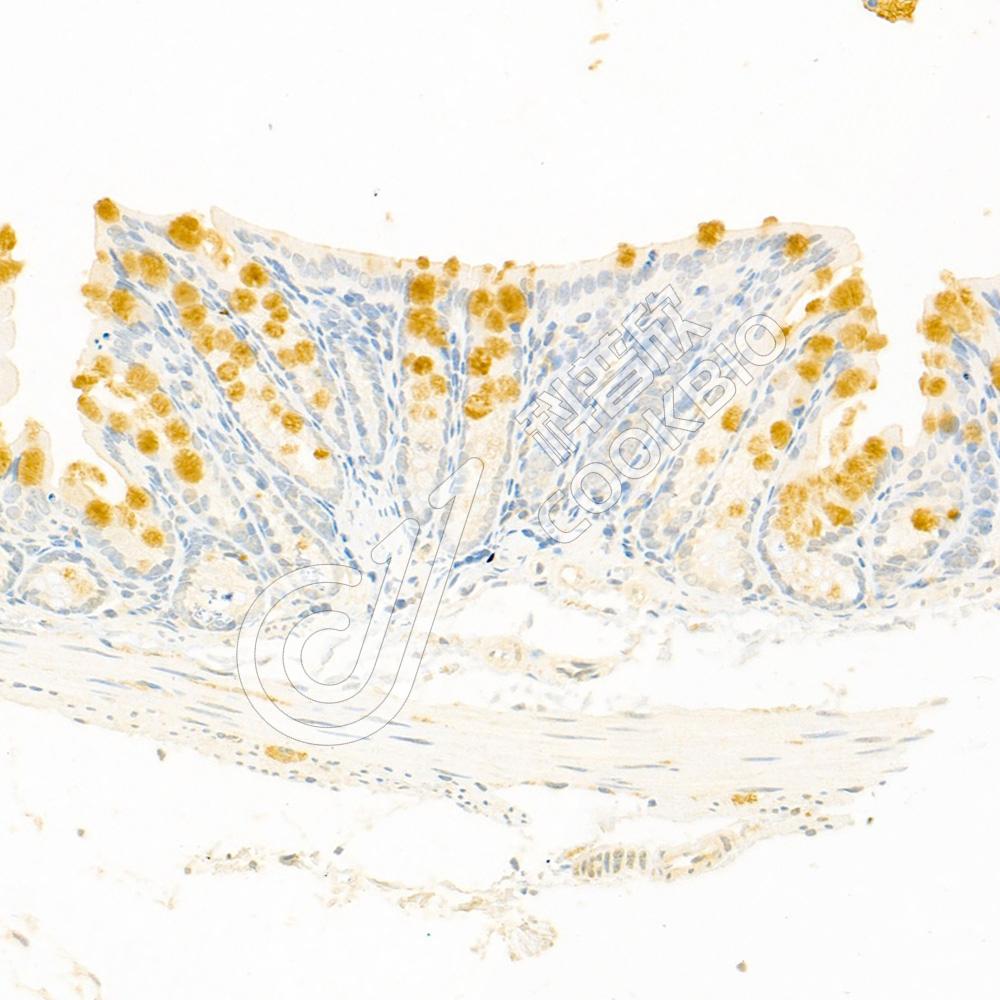

IHC检测SCN4B蛋白(货号 K1334788).

样品: 小鼠脑, 4%多聚甲醛 (货号KSG1101) 固定12-24小时.

抗原修复: 柠檬酸抗原修复液(干粉, pH 6.0) (KSG1201), 98℃, 20分钟.

—抗: 1: 3000稀释, 4℃ 孵育过夜.

二抗: S-vision免疫组化多聚二抗(山羊抗兔),即用型 (货号KB3906), 室温孵育20分钟.

样品: 大鼠脑, 4%多聚甲醛 (货号KSG1101) 固定12-24小时.